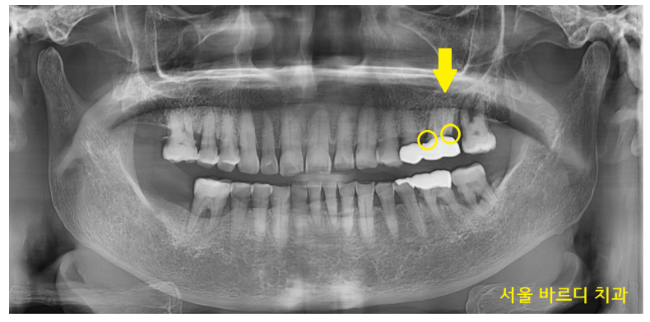

검진을 위해 X-RAY를 촬영해 보았더니

보철 수명이 다 된 것이 보이네요~

두 가지 문제가 있었습니다.

첫번째, 잇몸도 많이 내려가

맨 끝 치아는 흔들려 강일역 임플란트가 필요

두번째, 보철을 씌운 치아는 충치가 생긴 게 확인이 됩니다.